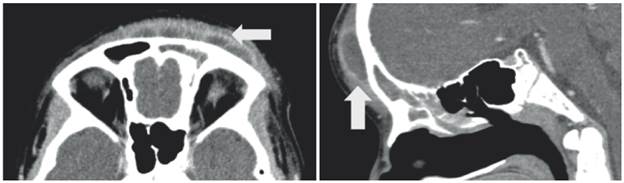

Tomografía de SPN en cortes axial y reconstrucción sagital, donde se aprecia material con densidad de tejidos blandos en seno frontal, relacionado con colección liquida prefrontal con realce periférico (flechas).

Figura 3: Tomografía de SPN en cortes axial y reconstrucción sagital, donde se aprecia material con densidad de tejidos blandos en seno frontal, relacionado con colección liquida prefrontal con realce periférico (flechas).